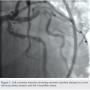

The left circumflex was approached first and no vessel preparation was performed. A stent was not able to be delivered despite aggressive predilation and double wiring, which included rupturing several balloons (Figure 2). Upon withdrawing the stent after a failed delivery attempt, the stent was sheared off the balloon and dislodged in the proximal circumflex and into the left main artery (Figure 3). At that point, the decision was made by the operator to stent next to this first stent to pin it up against the wall of the circumflex, “excluding” it. This was done successfully (Figure 4).